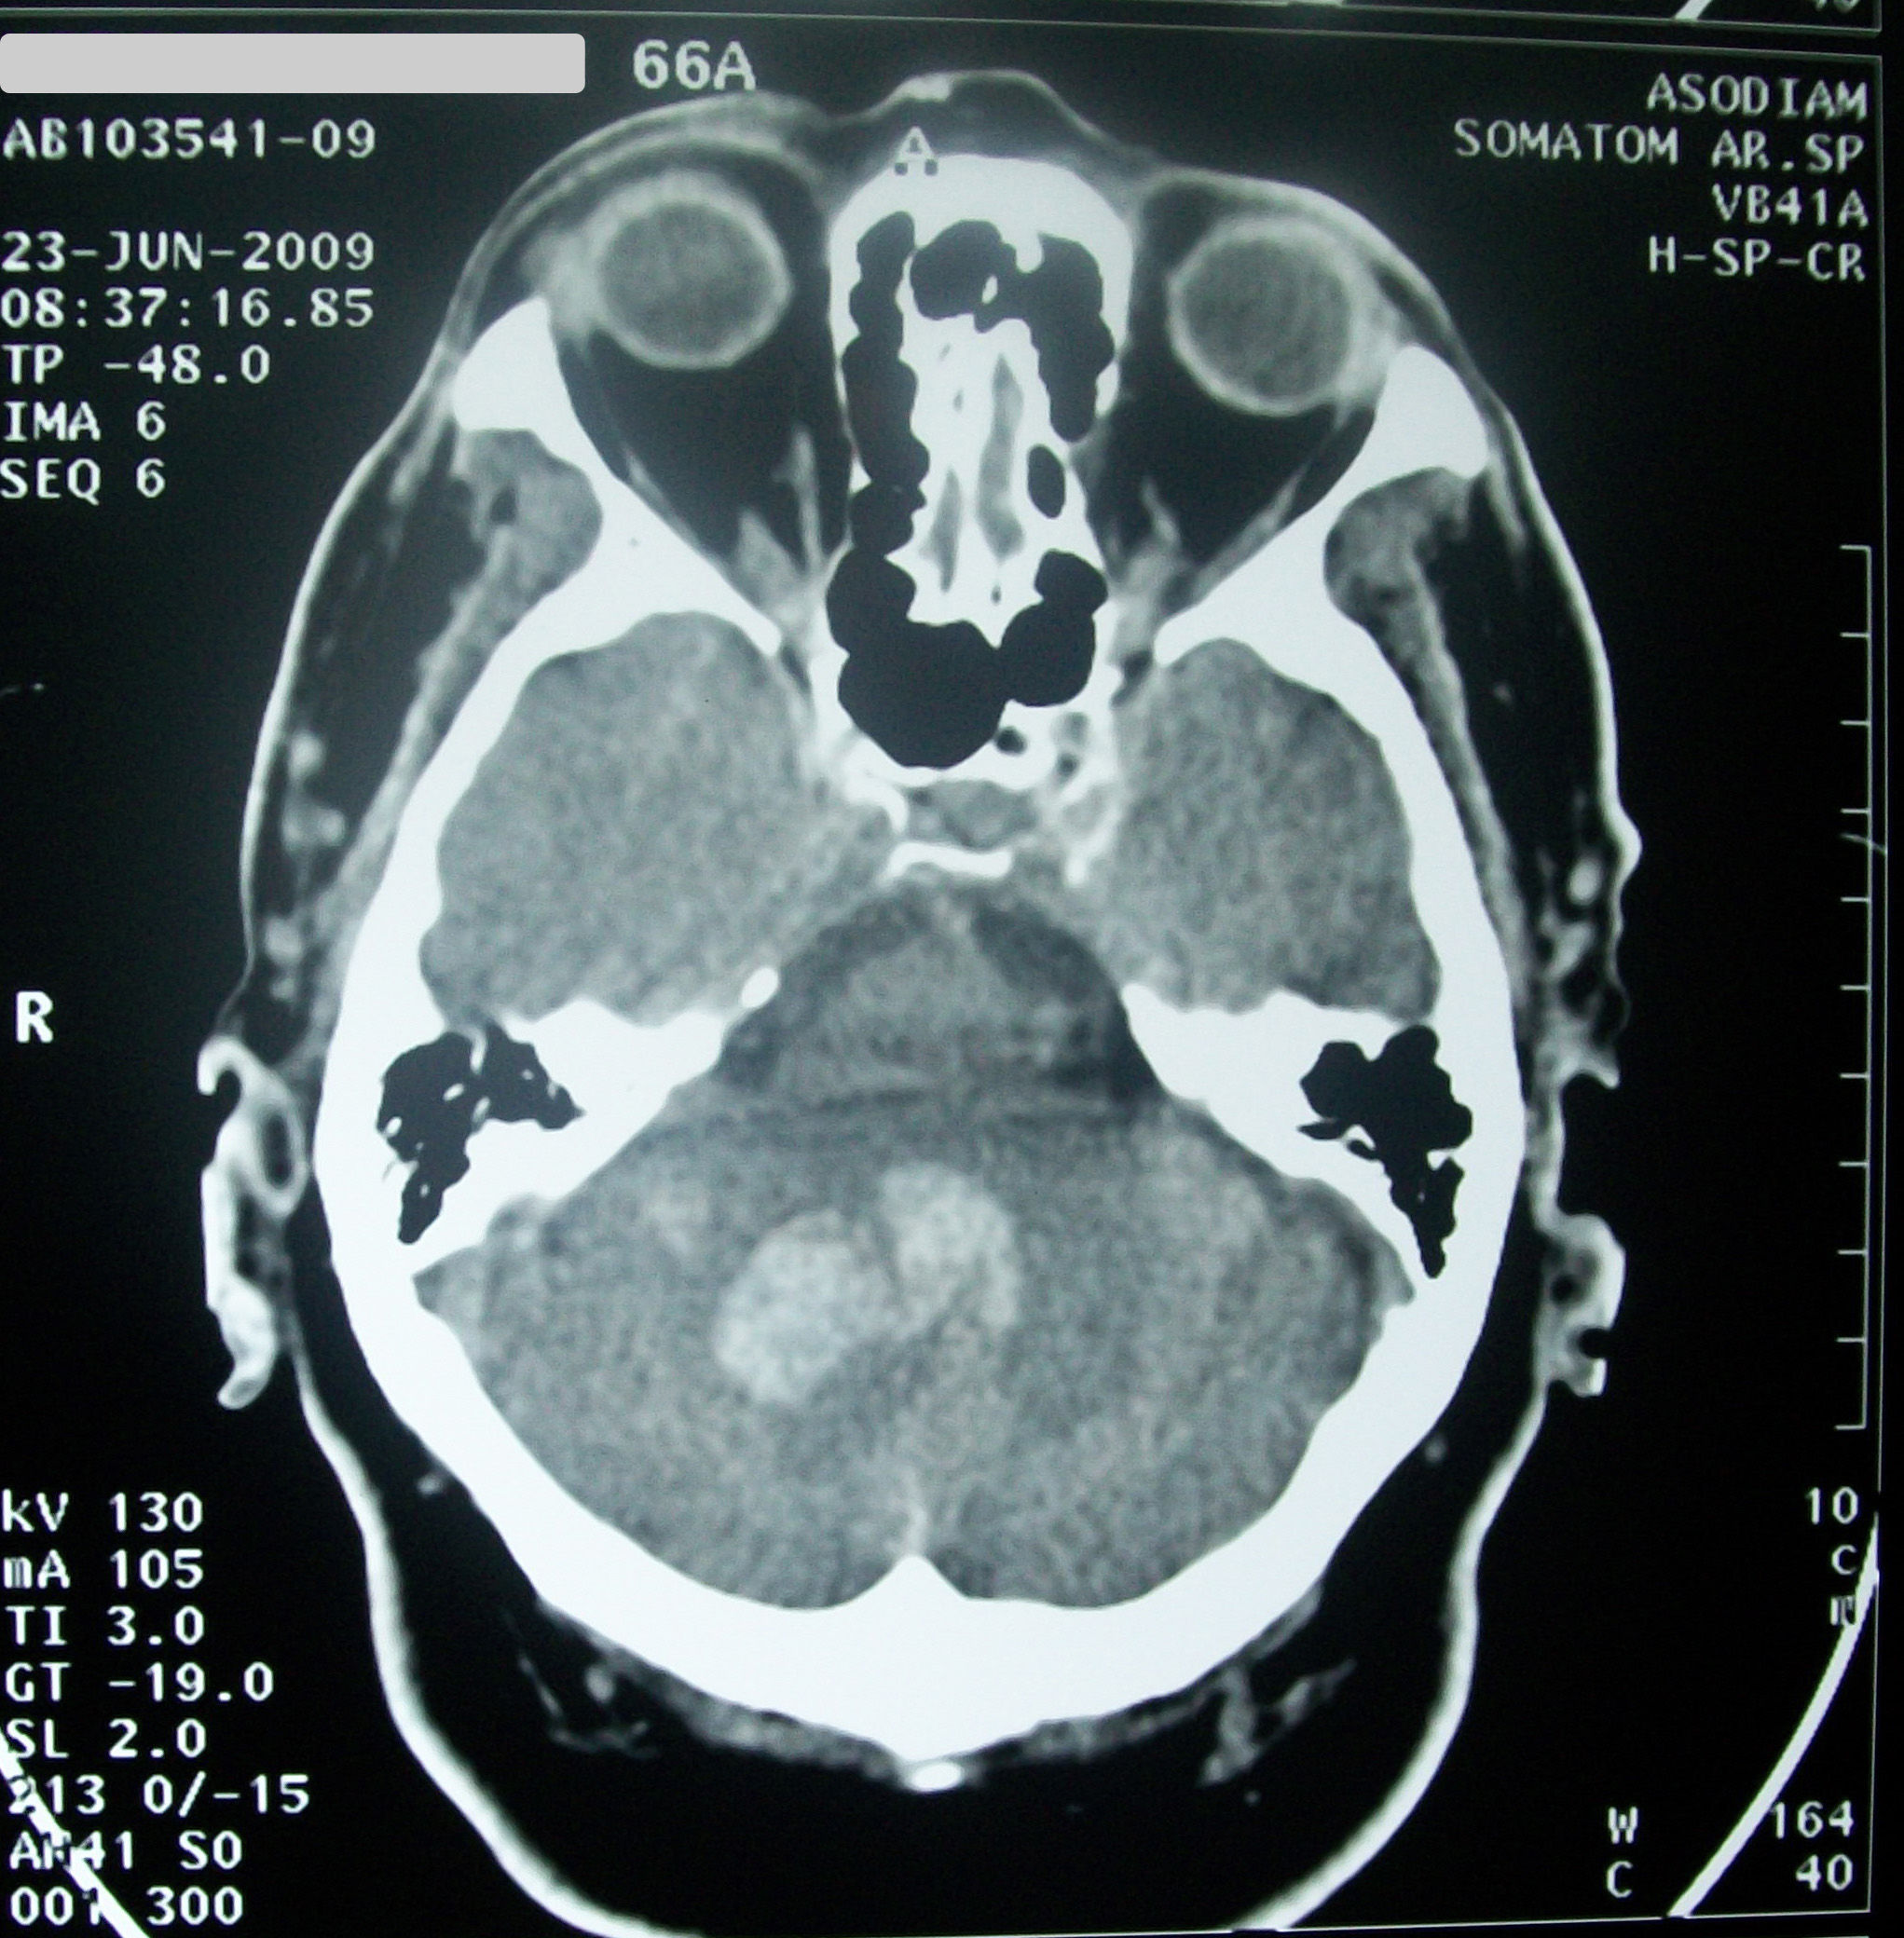

Imágenes

Query / Retrieve

Permite hacer búsquedas en PACS y recuperarlas

Formato DICOM

Cabecera

Cuerpo de datos de imagen

Puede tener múltiples fotogramas